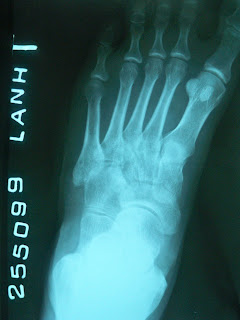

Đây là trường hợp một bênh nhân nam 31 tuổi bị tai nạn giao thông। Bệnh nhân vào viện ngay sau khi bị tai nạn। Bệnh được chẩn đoán là gãy xương đòn, gãy xương bàn tay trái। Bệnh nhân đã dược xử trí: mang đai số 8, bó bột cẳng bàn tay trái (xem hình)। Bệnh nhân nằm viện 2 ngày rồi xuất viện với lời dặn: tái khám sau một tháng।

Lần này, bệnh nhân đến bệnh viện thành phố Pleiku khám bệnh. Các hình ảnh trên đây ghi lại tình trạng khi bệnh nhân đến khám ( Gãy kín X।đòn trái, đầu dưới x।trụ trái, x।bàn 3,4 tay trái) Và hình ảnh KHX xương đòn Trái। Tình trạng tay trái không cử động được thì bệnh nhân không biết rõ có từ ngay sau khi bị tai nạn hay không.